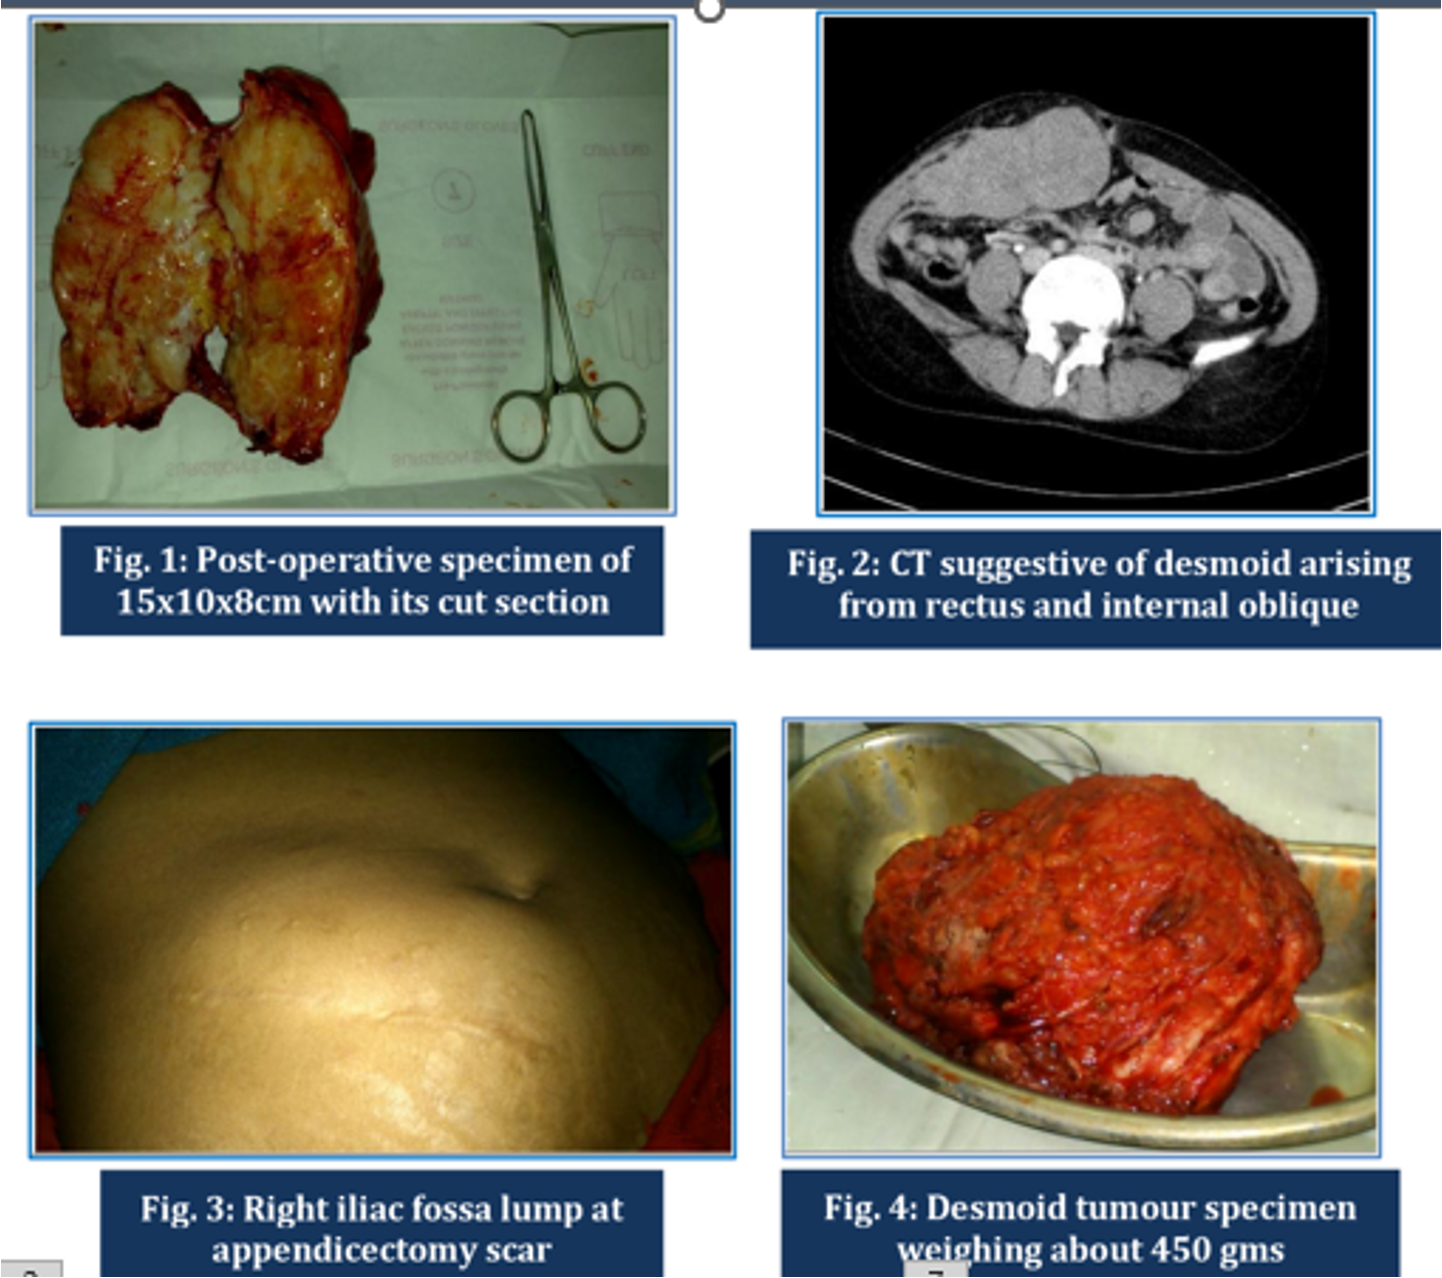

- Fibromatosis/ neoplasm: from fibroaponeurotic part of rectus abdominis.

- Diagnosis: CT or MRI for delineation, core needle biopsy.

- Treatment: Wide local excision. Local recurrence high if margins are involved.